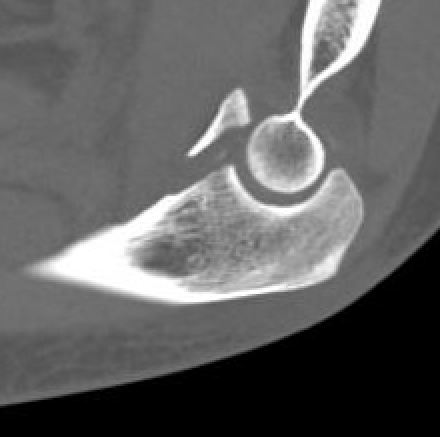

Anteromedial coronoid facet fragment

- associated with varus posteromedial rotational force

- associated with tear of lateral ulna collateral ligament (LUCL)

Medial approach and buttress plate with LCL repair